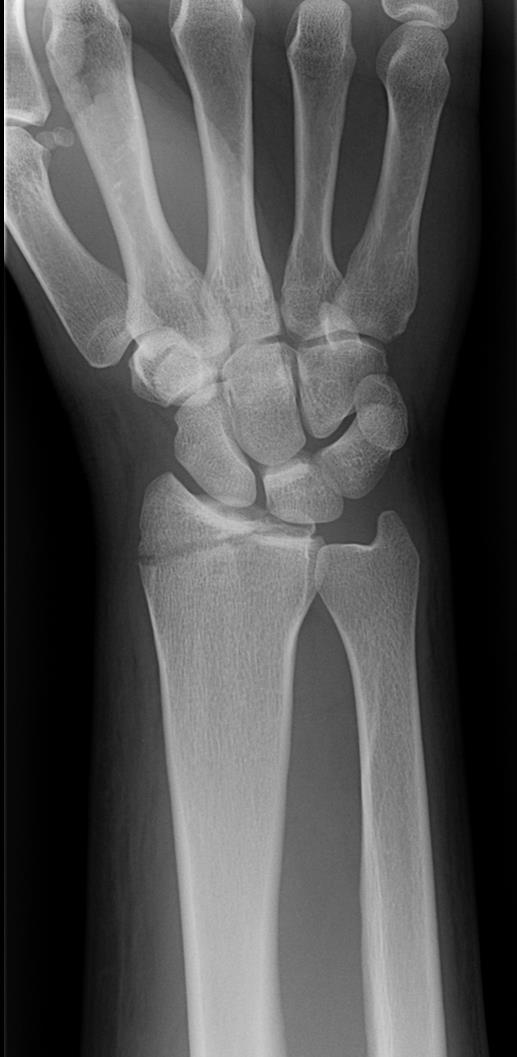

• Smith's fx

• Volarly angulated, extra-articular fx